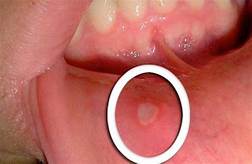

L’aphte est un petit ulcère qui apparaît dans la bouche , aussi bien sur la langue, l’intérieur des joues, les gencives, l’intérieur de la lèvre et parfois également sur le palais